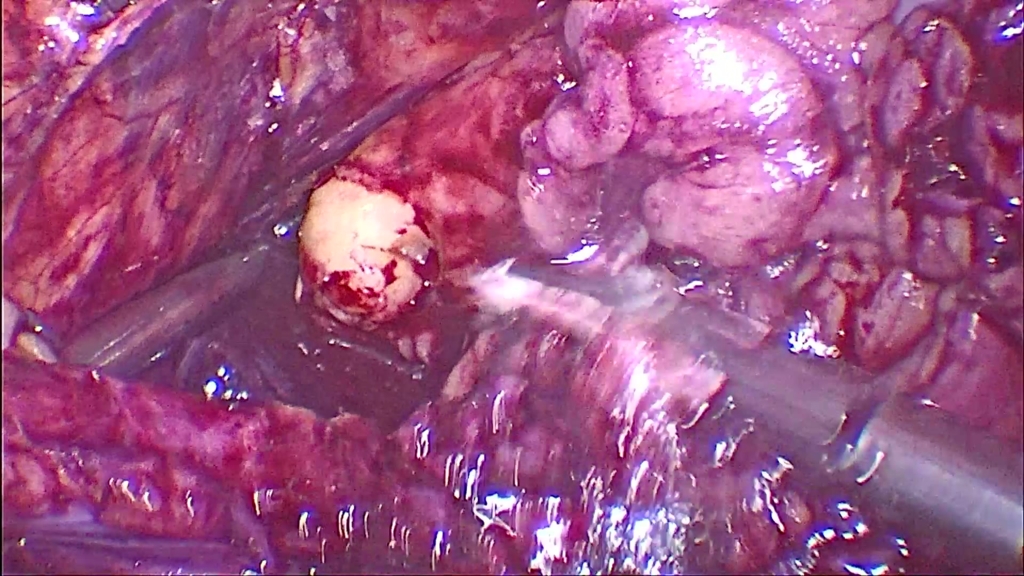

Кишечная пластика правого мочеточника